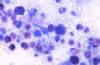

what inflammation type is shown here

eosinophilic